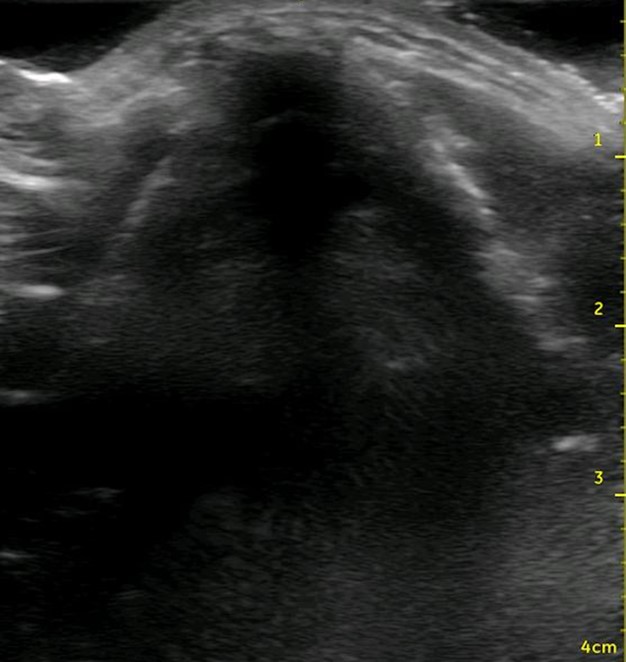

Figure 2. Ultrasound view of the thyroid cartilage in the transverse plane.

In contrast to native cartilage, which is hypoechoic with posterior shadowing, the plastic model of the thyroid cartilage and cricoid cartilage appear hyperechoic with more dense posterior shadowing (below). This model performs well as an ultrasound-guided cric training model. It has realistic anatomy. It models a patient with difficult to palpate anatomy, which are patient who may be difficult to intubate and may be more likely to need cricothyrotomy in the first place. The overlying skin and pre-tracheal ballistic gel can be easily and quickly replaced for the next operator in a training setting. The model allows for performing all the steps of cricothyrotomy including passing the bougie and ETT. The model is durable and re-usable.